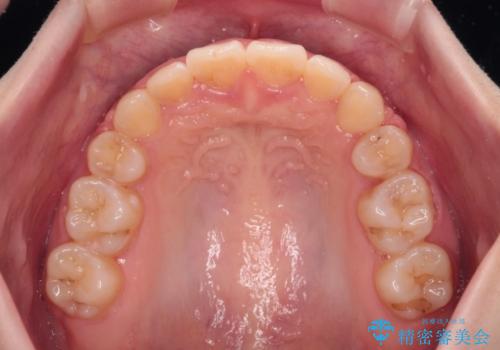

- 上下の前歯が突出しており、口が閉じにくいとのことで来院された患者様です。

上下前歯が著しく前突している状態であったので、上下左右の第1小臼歯4本を抜歯し、ワイヤー装置にて矯正治療を行うこととしました。

舌の突出癖があり、前歯の移動量も多くなるため、治療期間は長くなると予想されましたが、13ヶ月という予定の半分程度の期間で終えることができました。